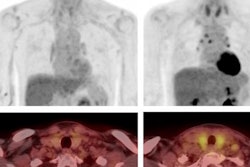

Both single and dual-tracer PET/CT were tolerated well by all patients, without any recorded adverse reactions or side effects, and all primary tumors could be clearly detected on both scans. However, in one patient, F-18 FDG revealed metastasis in only one mediastinal lymph node, whereas dual-tracer accumulation revealed two additional lymph nodes of the same drainage region.

One mediastinal lymph node of another patient showed discrete nonsuspicious F-18 FDG tracer accumulation, but suspiciously high dual-tracer accumulation. In addition, dual-tracer PET/CT displayed a higher number of liver metastases than F-18 FDG-PET/CT alone in a patient with a metastasis in the adrenal gland.

(A) Single-tracer PET/CT with F-18 FDG showing fused images in the axial plane of a primary tumor at the gastroesophageal junction with a metastasis in the left adrenal gland and liver metastases. (B) Maximum intensity projection (MIP) of single-tracer PET images displaying high uptake in brain tissue, tracer accumulation around the injection side at the right elbow, lymph node metastasis in the left upper mediastinum, multiple abdominal lymph node metastases, and liver metastases. An additional benign accumulation of FDG is visible, caused by right-sided thoracolumbar osteoarthritis. (C) Transverse section of fused dual-tracer F-18 FDG and Ga-68 FAPI-46 PET/CT of the same patient. (D) As all images were visually normalized to the uptake of the liver, MIP of dual-tracer PET/CT in the same patient shows a less pronounced tracer accumulation in the brain tissue, compared to single-tracer PET/CT. In addition to lesions detected with single-tracer PET/CT, further abdominal lymph node metastasis and liver metastases are visualized via dual-tracer PET/CT. The focal tracer accumulation in the right vein angle is due to intravenous tracer accumulation from the former tracer depot at the right elbow. Image courtesy of the Journal of Nuclear Medicine.Since the diagnostic performance of Ga-68 FAPI-46-PET/CT is best shortly after injection and F-18 FDG-PET/CT is currently the gold standard, the authors so far recommend the injection of Ga-68 FAPI-46 as a second tracer after the F-18 FDG-PET/CT scan.